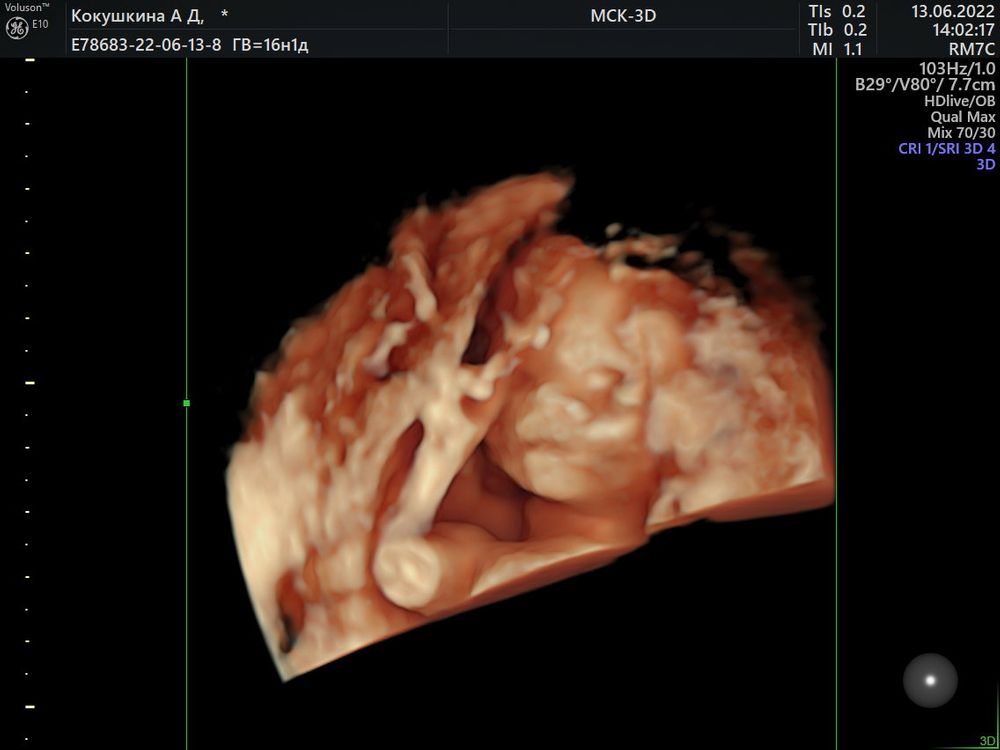

Узнали пол малыша в 16-17 недель🥰

Пузатенький такой)))Поздравляю вас))